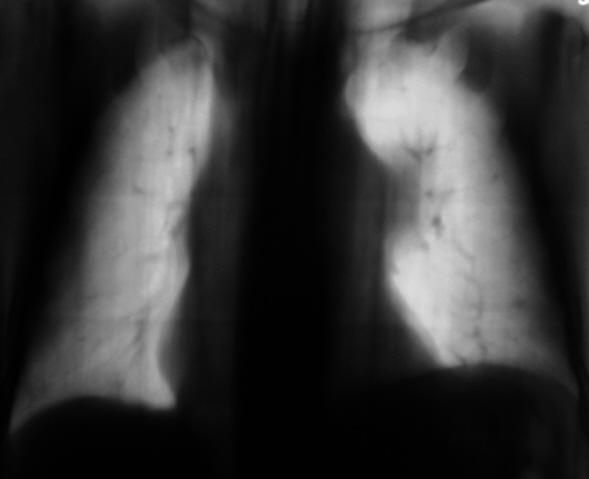

103.K.F..JPG

Сами знаете, Валентин Львович, к онкологам (картина периферичевого рака в/доли слева)... Кроме того, под подозрением л/узлы в правом корне и средостенье (КТ). Справа, думаю, старые переломы ребер...

Не исключено, что все изменения, которые видны в средостениии и левом корне - метастазы. Где первичная пока не ясно. Парез левого френикуса?

Согласен с Вами. Высоковат купол диафрагмы слева.